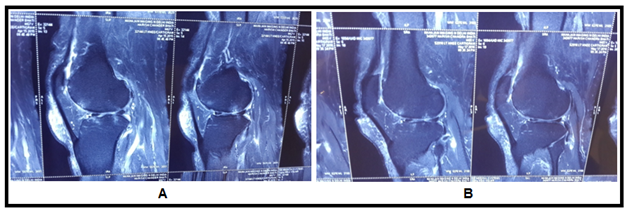

Figure 4 (A) MRI Images show subchondral cyst in femur with multiple breach in articular cartilage, (B) images show disappeared subchondral cyst with healed cartilage breach at one year follow up after stem cell transplantation.

The MRI study at the last follow−up visit (1 year) showed an important improvement in the cartilaginous tissue in different parameters. Patients showed partial restoration of medial joint space of knee with disappearance of subchondral bone edema with increased thickness of articular cartilage which was more smooth and non porous in contrast to pre BM−MSC transplant stage. The pre and post BM−MNCs transplant MRI/x−Ray studies showed notable changes in cartilage defects (Figures 4‒8).